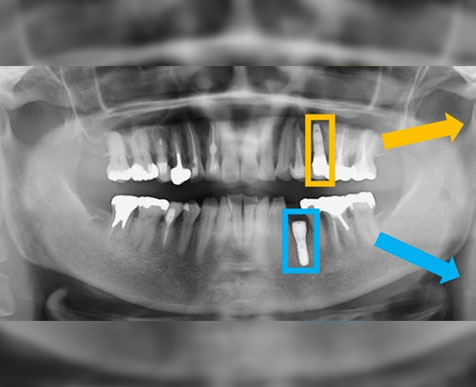

AI implant localization

AI implant pose estimation.